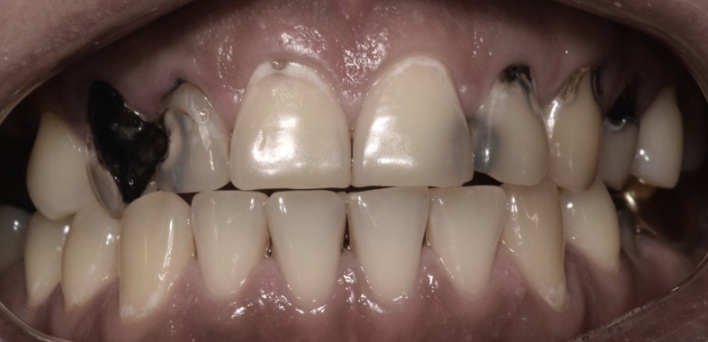

※ 더서울치과의원은 의료법을 준수하며 위 케이스는 실제 환자의 동의를 얻은 사례로 치료 전, 후가 동일한 환경에서 촬영되었습니다.

환자 케이스에 따라 부작용이 발생할 수 있습니다. 이 부분은 의료진의 충분한 상담과 체크를 통해 예방하고 줄일 수 있습니다.

[심미치료 부작용] 시술 후 치아 시림, 보철물 파손 등의 부작용이 발생할 수 있어 개인별 치아 상태에 따른 정확한 진단과 사후 관리가 중요합니다.